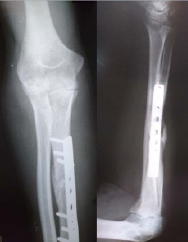

At six weeks, Kirschner wires and slab was removed. Patient was followed up then at 3rd and 6th. Postoperatively at six months [Table/Fig-3], ulna united and patient has achieved flexion from 50 to 115 degrees at elbow and a 120 degrees supination pronation arc [Table/Fig-4,5,6]. At each visit check x-ray was done to see for bony union and radiocapitellar congruency. DASH score (Disabilities of Arm, Shoulder and Hand), Broberg-Morrey index score and range of movement were recorded at each visit to see the functional improvement [Table/Fig-7].

Ulna union and reduced radial head at six months..